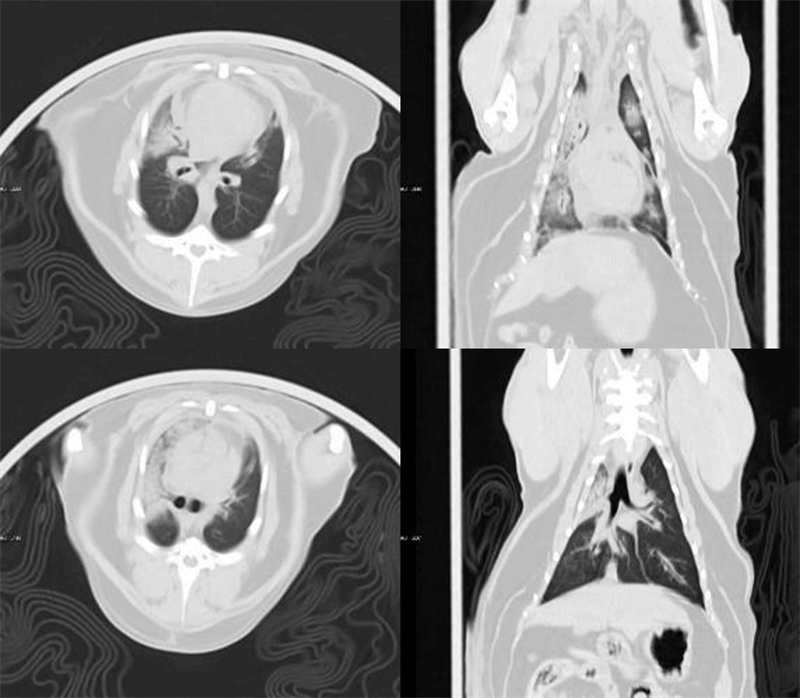

Uygulama Görüntüleri